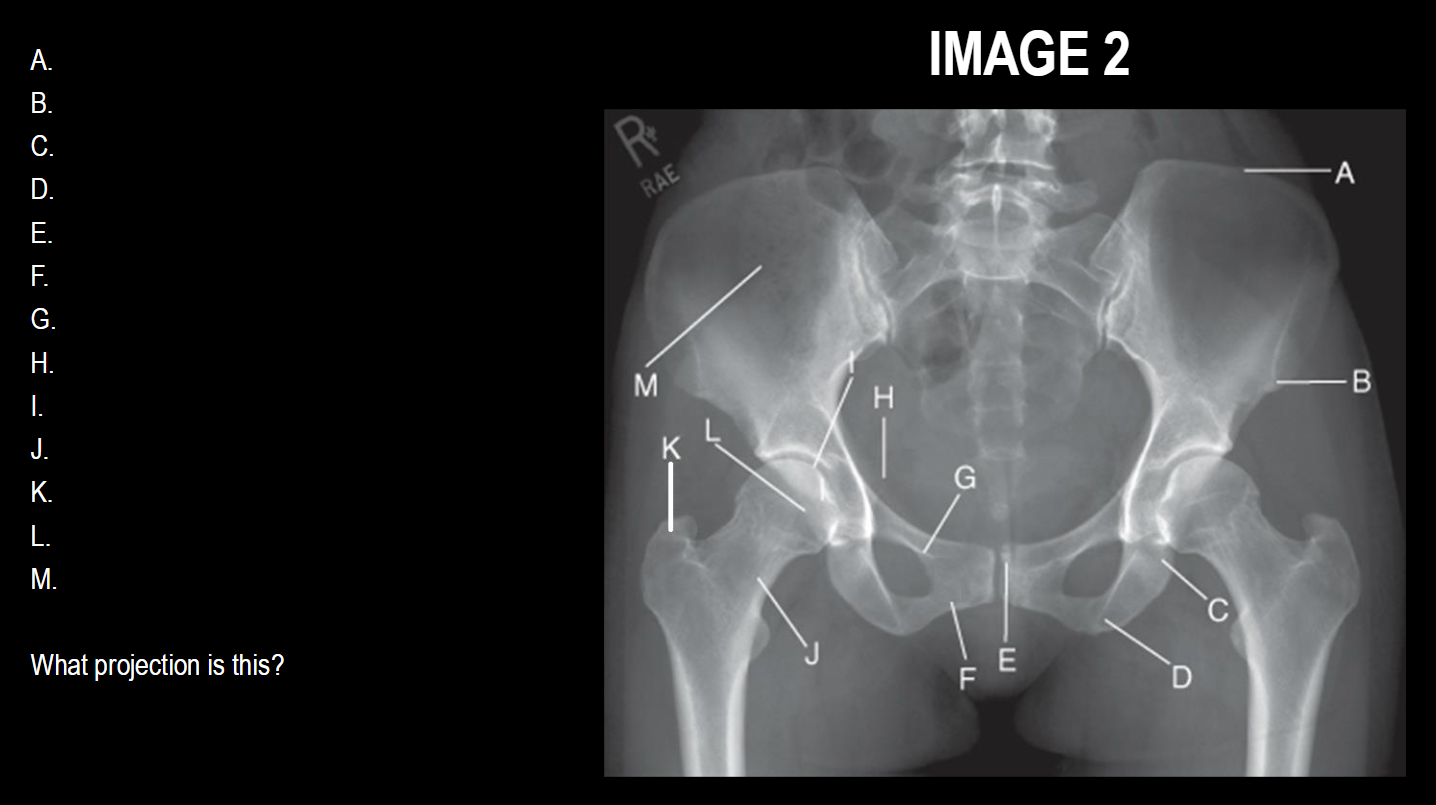

A

Ala/wing of ilium

B

Acetabulum

C

Femoral head

D

femoral neck

E

Greater trochanter

F

Body of femur

G

Lesser trochanter

H

Body of ischium

I

Isvhial tuberosity

J

Obturator foramen

K

Superior ramus of pubis

L

Inferior ramus of pubis

M

Pubic symphysis

N

Pelvic brim

O

Ischial spine

What projection is this

AP Pelvis